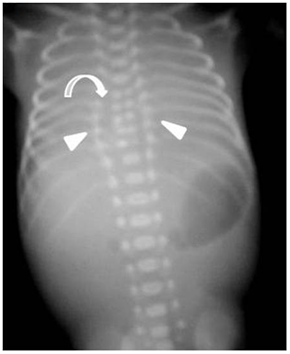

Figure 4 Post-mortem X-ray of the fetus: Local widening of the interpedicular distance in thoracic vertebrae (arrows) associated with partial sagittal partition (thick curved arrow) from T6 to T10.